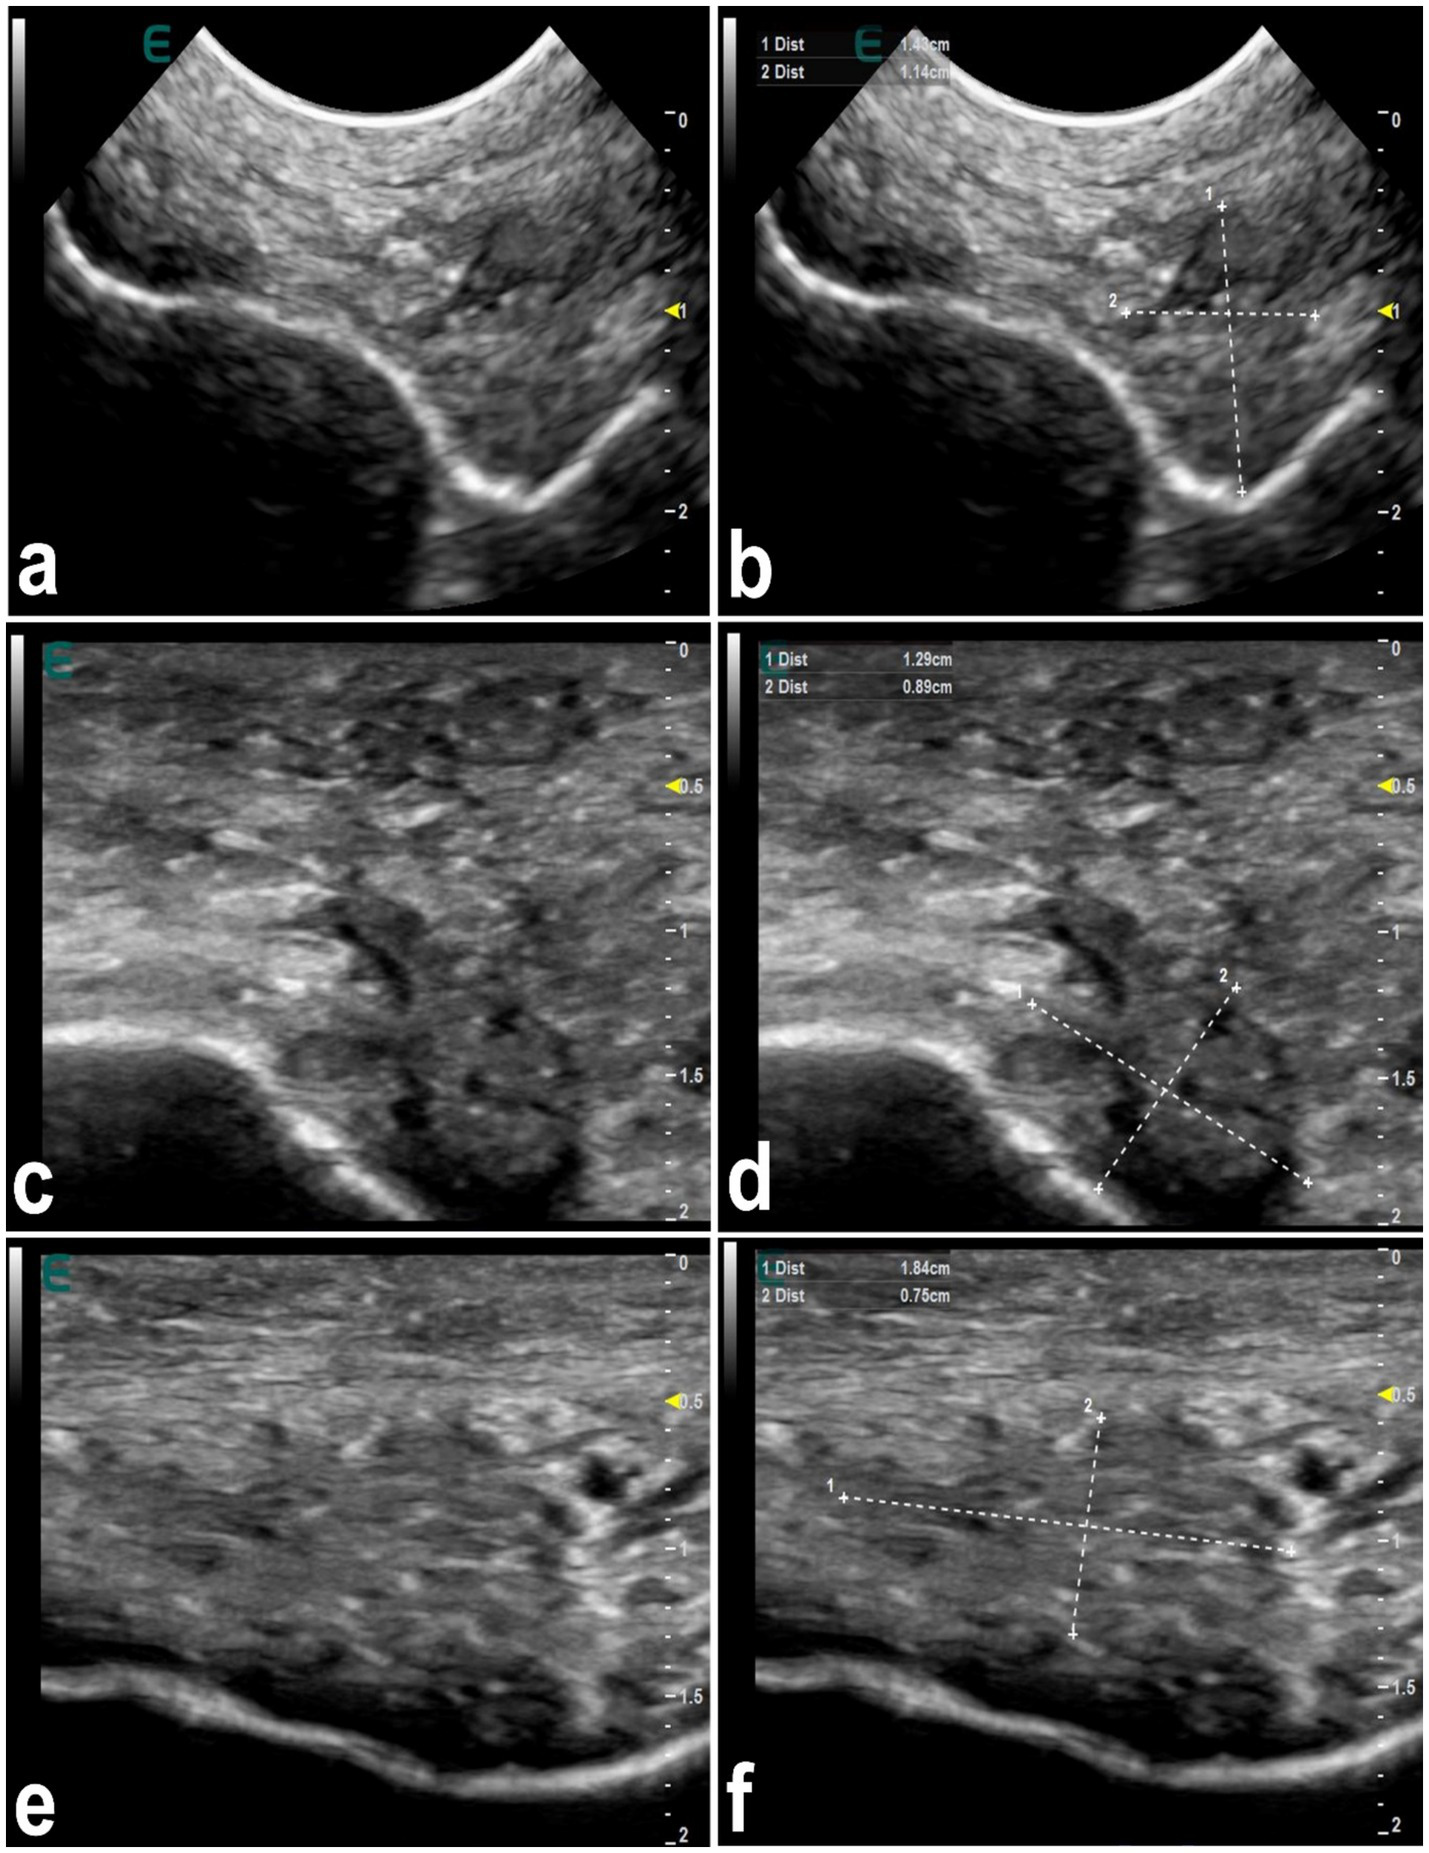

Figure 5 shows mapping of the lips in a healthy camel showing different locations where injected filler materials are commonly injected. In healthy camels, the dermis appears hyperechoic, contrasting with the hypoechoic subcutaneous tissue (16). Filler substances, even those approved by regulatory agencies, can cause in humans detectable changes in tissue structure (63). Injected fillers in dromedary camels typically appear as anechoic or hypoechoic areas on ultrasound, presenting as single or multiple deposits of varying size. In affected camels, the boundary between the dermis and subcutaneous tissue becomes indistinct (Figure 6). Fillers in the firm edges of the lips exhibit hypoechoic signals, with the overall sonographic pattern of injected lips appearing heterogeneous (Figure 7). Lip nodules are visualized as either isoechoic structures with a hypoechoic rim or as hypoechoic lesions with an echogenic center (Figure 8).

Ultrasonographic appearance of injected fillers in the upper lip of 3 female dromedary camels (a,c,e). The injected filler appears anechoic to hypoechoic and was imaged in the form of small or large, single or multiple deposits. It is difficult to distinguish the subcutaneous tissue from the dermis. Images (b,d,f) represent a schematic representation of the images (a,c,e), respectively [Reproduced from (44)].

Figure 7

Ultrasonographic features of hardened tip of the lips in 3 dromedary camels with injected fillers (a,c,e). The injected filler appears hypoechoic and the scanning patterns of the injected lips appear heterogeneous. Images (b,d,f) represent a schematic representation of the images (a,c,e), respectively [Reproduced from (44)].

Figure 8

Ultrasonographic features of lip nodules in 3 camels as a result of filler injections (a,c,e). They appear as either isoechoic with a hypoechoic rim or hypoechoic with an echogenic center. Images (b,d,f) represent a schematic representation of the images (a,c,e), respectively [Reproduced from (44)].